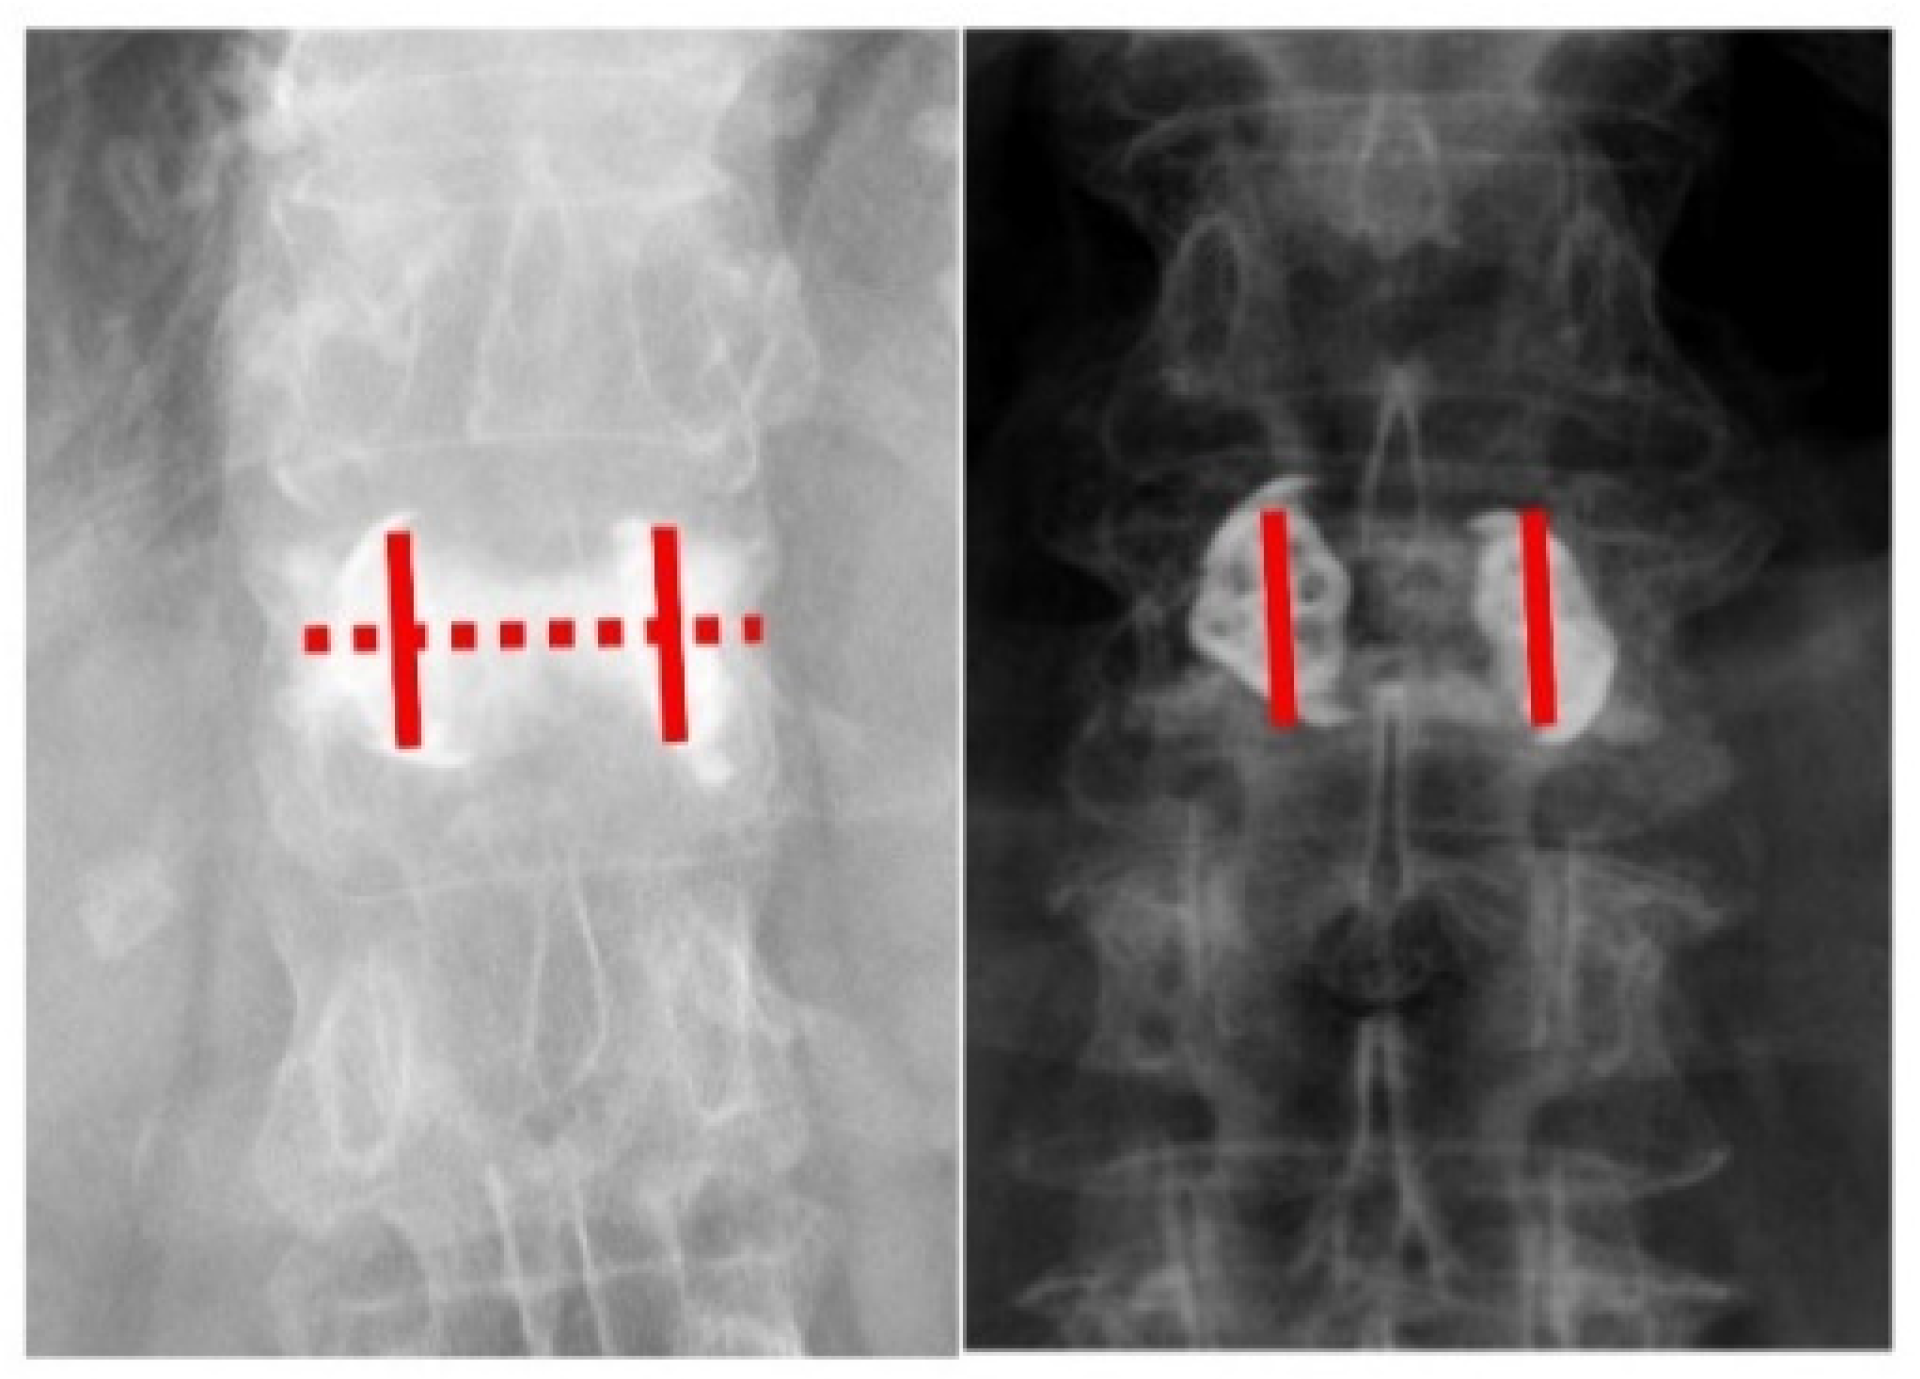

Figure 2. (Left) The AP view of the radiographic image shows a positive double cross sign. The bone cement expands vertically along the bilateral SpineJack system, and across the midline of the vertebral body. (Right) The AP view of the radiographic image shows a negative double cross sign. The bone cement expands vertically along the bilateral SpineJack system without spreading across the midline of the vertebral body.

Image assessment that included anterior, middle, posterior vertebral body heights, and regional and local kyphotic angles was carried out before and after the operation (Figure 1). We defined the “double cross sign” as bone cement that expanded vertically along the bilateral SpineJack system and across the midline of the vertebral body in the anteroposterior (AP) view of the radiographic image (Figure 2). The assessment of the postoperative radiographic image that met the criteria for double cross sign was also conducted and recorded by the same single senior orthopedic spine surgeon (C-CH). In addition, the angle between the two expanded devices was recorded immediately after the surgery, and at the latest postoperative radiographic follow-up (Figure 3).

Kyphoplasty with the SpineJack system was able to restore vertebral height and stabilize the vertebra with an injection of bone cement. The goal of this study was to seek a reliable assessing method during the surgery in determining the minimum amount of bone cement required for the SpineJack system to restore vertebral height and stabilize the vertebra. We defined the “double cross sign” as bone cement that expanded vertically along the bilateral SpineJack system, and spread across the midline of the vertebral body as viewed in the anteroposterior (AP) view of the radiographic image. Sixty-five patients aged 74.5 ± 8.5 years with vertebral compression fracture were included in the study. Patients with a positive double cross sign had better ODI score than those without the double cross sign (20.0 ± 6.9 vs. 32.3 ± 8.2; p < 0.001). Postoperative regional kyphotic and local kyphotic angle were significantly better in the positive double cross sign group (11 ± 8.8 degrees vs. 5.3 ± 3.2 degrees; p = 0.001/11.7 ± 6.2 degrees vs. 6.6 ± 4.1 degrees; p = 0.001, respectively). The more stable construct was built once the double cross sign was achieved during surgery. In this study, a convenient and intuitive method in identifying the minimum but sufficient quantity of injected cement during the SpineJack procedure was developed.